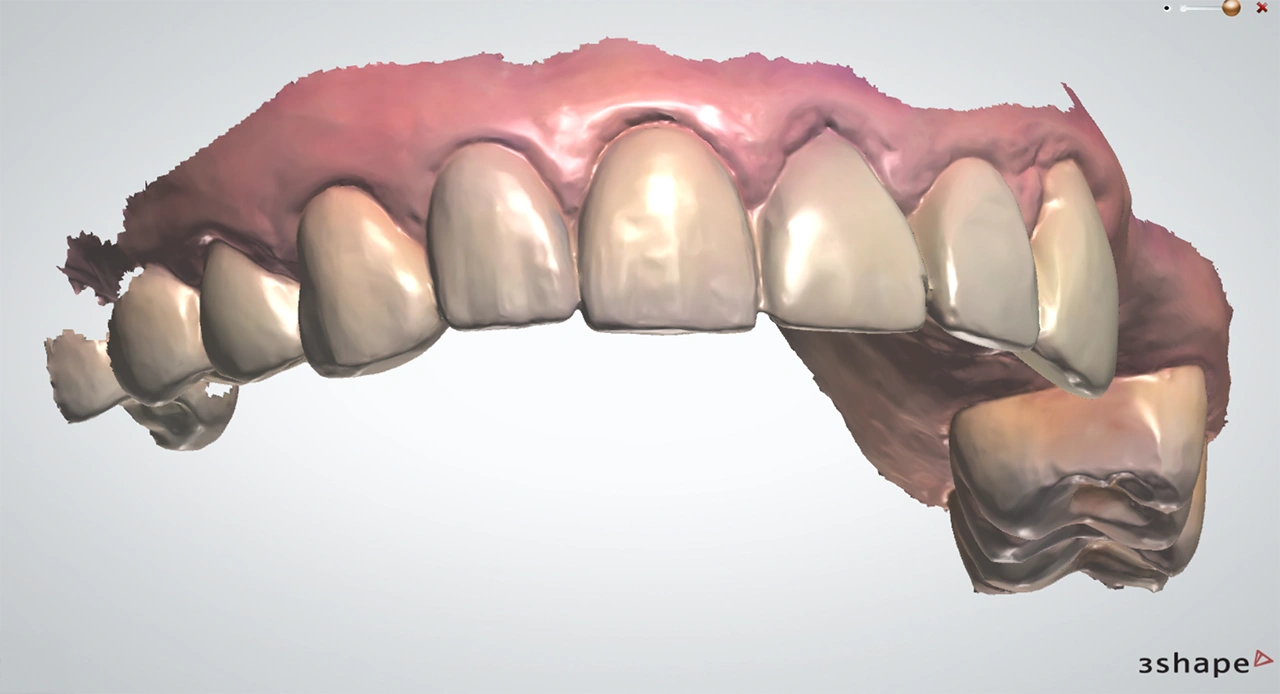

Цифровые слепки: конец «эпохи ложек»

Внутриротовой сканер (IOS) заменяет классические слепки. За несколько минут он создаёт 3D-модель зубов с точностью, которая не только не уступает, а часто и превосходит по качеству полученную аналоговым методом.

Систематический обзор Pesce P. et al., (2025) подтверждает: цифровые слепки в большинстве случаев дают равноценную или более высокую точность, особенно при сканировании под одиночные коронки или мостовидные протезы небольшой протяжённости.

Digital Smile Design: примерка новой улыбки до лечения

Это один из самых любимых этапов для пациентов. Digital Smile Design (DSD) позволяет смоделировать будущие реставрации ещё до начала лечения, подобрать форму, размер и цвет зубов, а главное — увидеть результат на экране и провести «тест-драйв» новой улыбки в полости рта.

Систематический обзор Jain A. et al., (2024) показал, что пациенты, которым выполняли DSD, были значительно более удовлетворены эстетикой и чаще рекомендовали лечение своим знакомым.